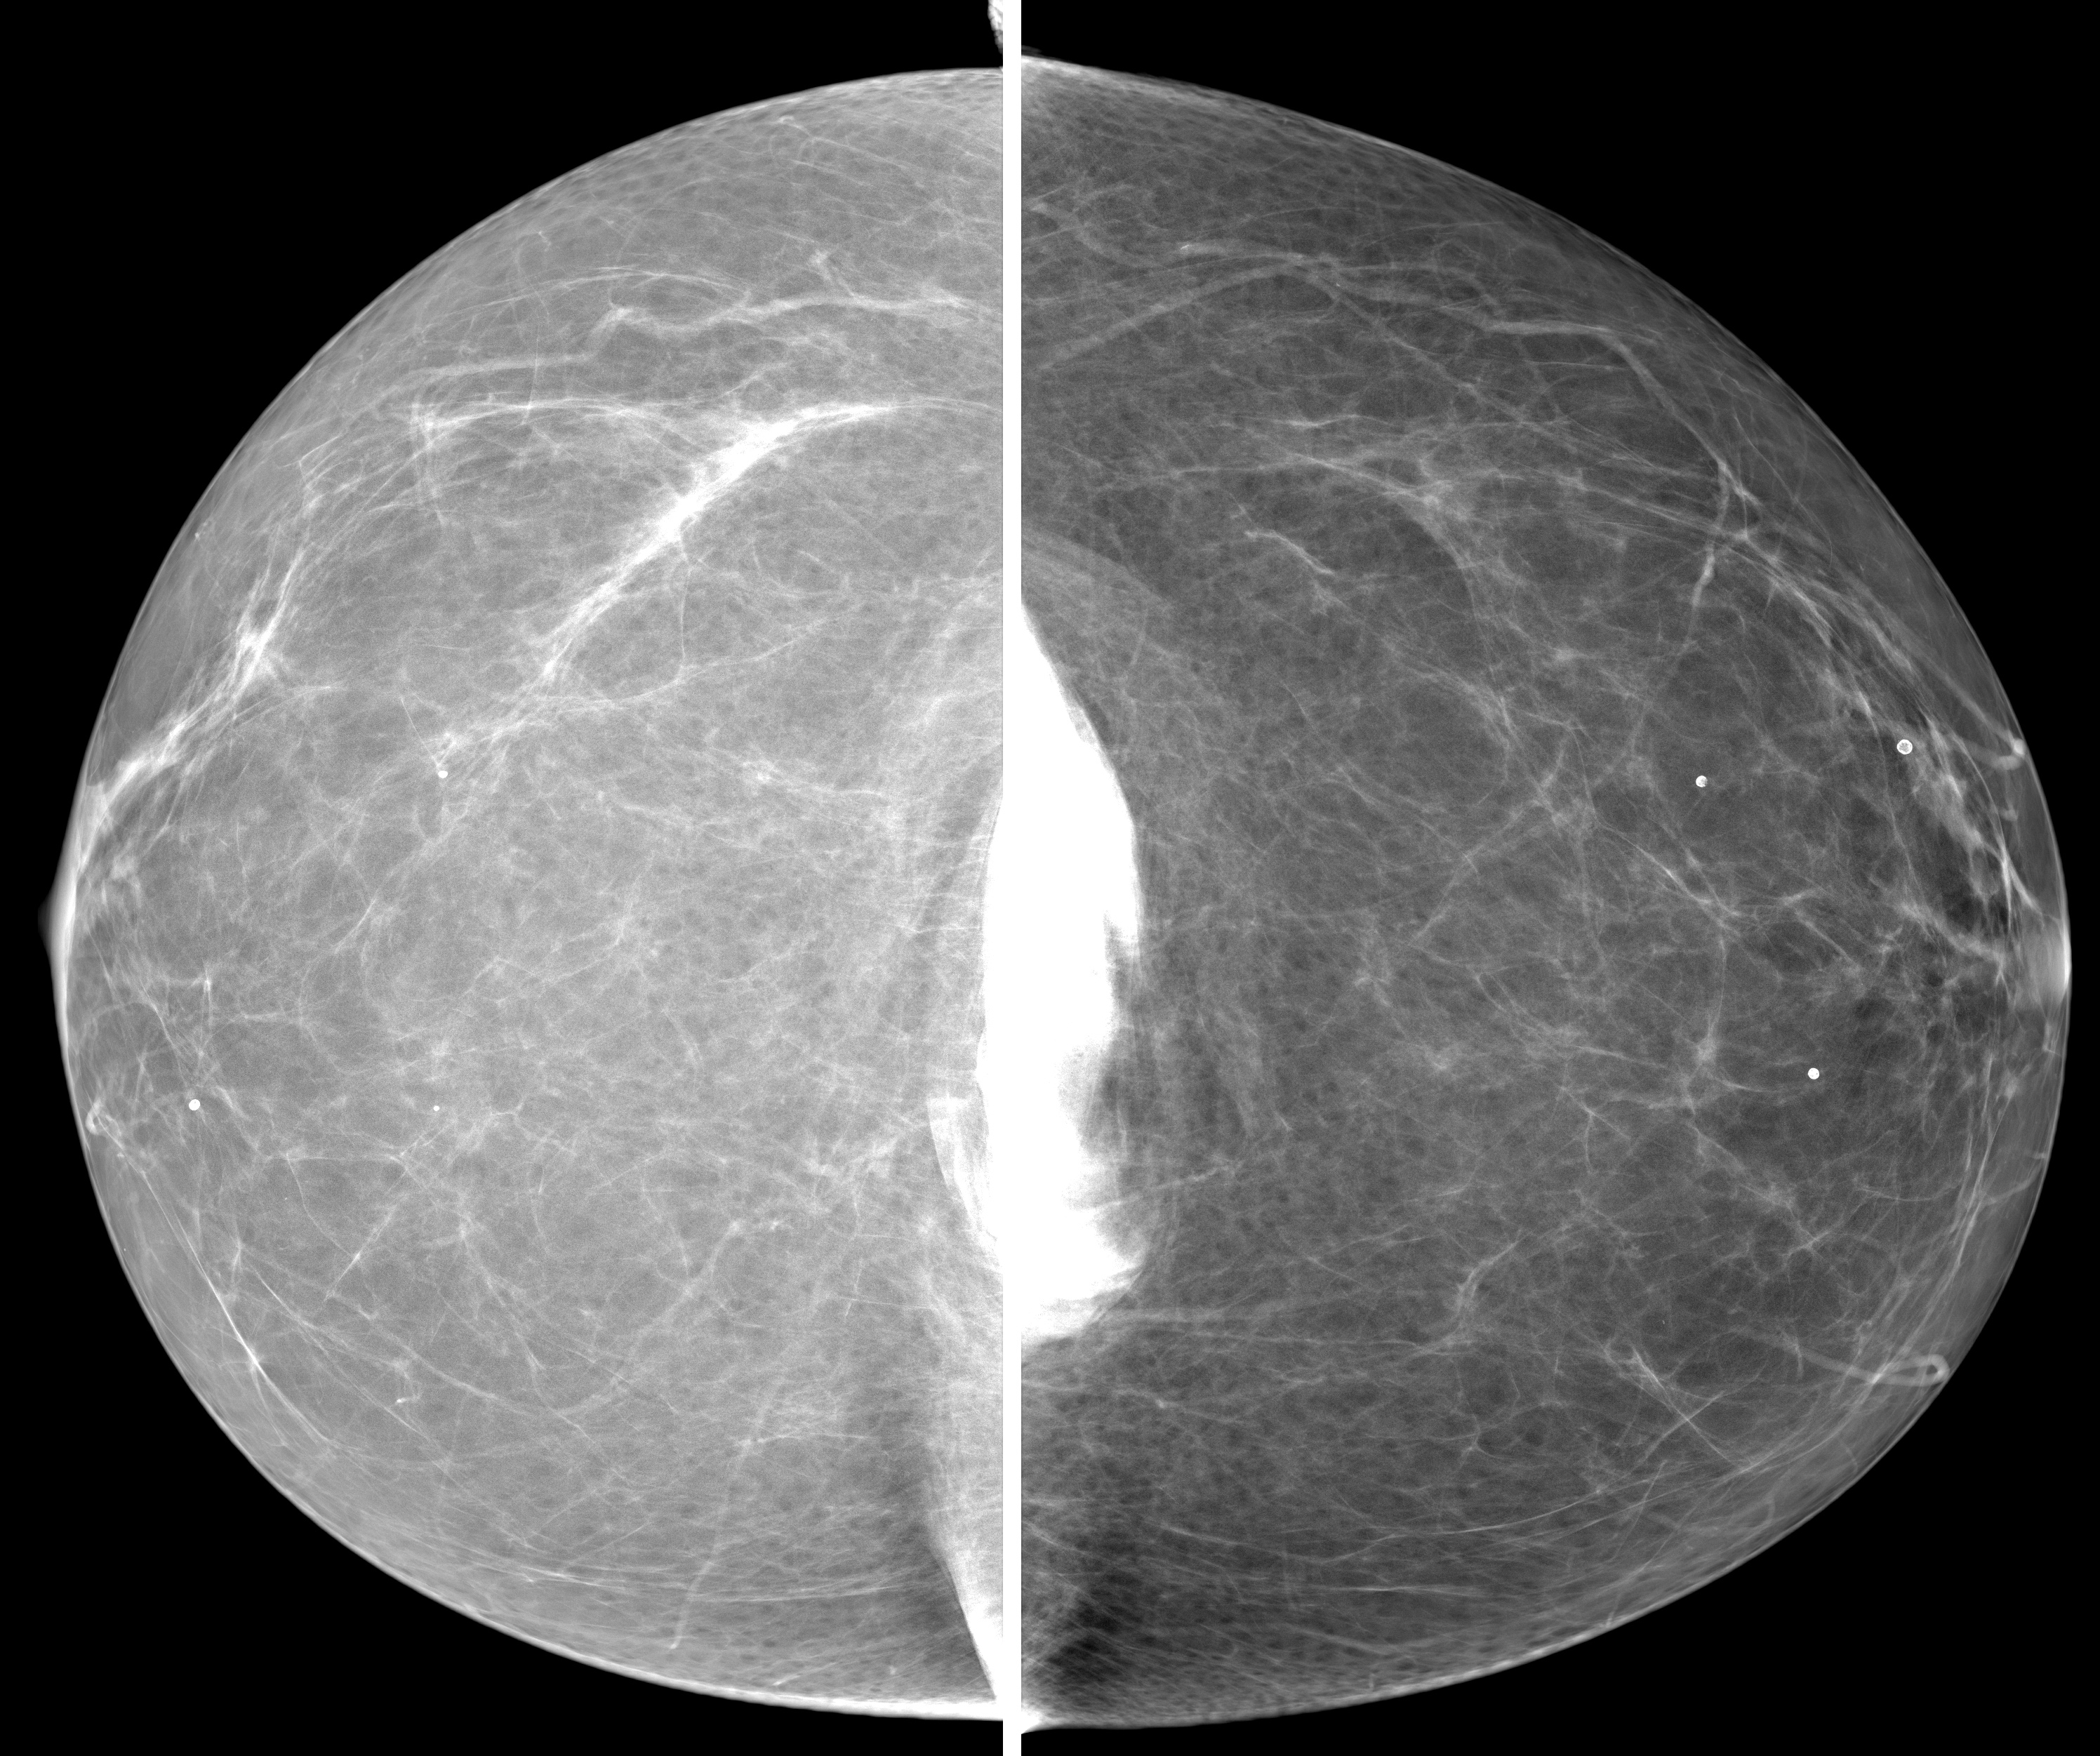

◂Breast Anatomy